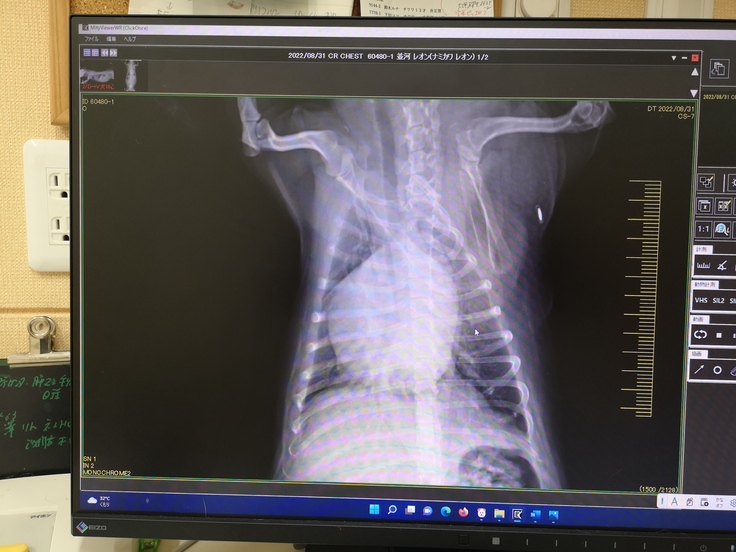

【僧帽弁閉鎖不全症】

この病気にはA~Dまでの五段階のステージがありますが、レオンは二番目に重篤なCです。

犬の心臓僧帽弁閉鎖不全病の手術が出来る施設は全国に数えるほどしかありませんが、その一つが名古屋にあります。

※動物病院から掲載許諾は得ています

その病院では【僧帽弁形成術】という非常に高度な術式を用います。